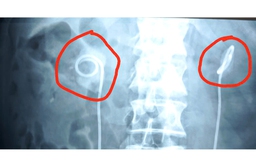

Sỏi bám đầy ống thông JJ sau 2 năm quên trong niệu quản